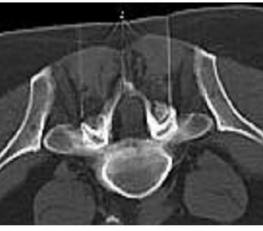

Sakrale Blockaden, Peridurale Blockaden

Bei der periduralen oder sakralen Blockade oder landläufig auch Rückenmarksnarkose genannten Infiltration und Überflutung des Nervenwurzelschlauchs (Kaudalsack) im Bereich der unteren Lendenwirbelsäule wird über einen kleinen Zugang im Kreuzbein (Hiatus sakralis) eine Kanüle oder ein Katheter in die Nähe des Nervenwurzelsacks vorgeschoben und dann ein Narkosemittel mit ggf. Beimengungen von Cortison oder einem Enzym appliziert.

Darunter soll es zu einer Blockierung der unteren Lenden- und Sakralnervenwurzeln, welche z. B. durch einen Bandscheibenvorfall oder durch eine Wirbelkanaleinengung gereizt sind, kommen. Die Schmerzen sollen reduziert werden und zudem eine Abschwellung der gereizten Nervenwurzeln erfolgen. Erfahrungsgemäß beträgt die Erfolgsquote 60-70%. Es werden 6-12 Injektionen in unterschiedlichen Zeiträumen erforderlich sein.